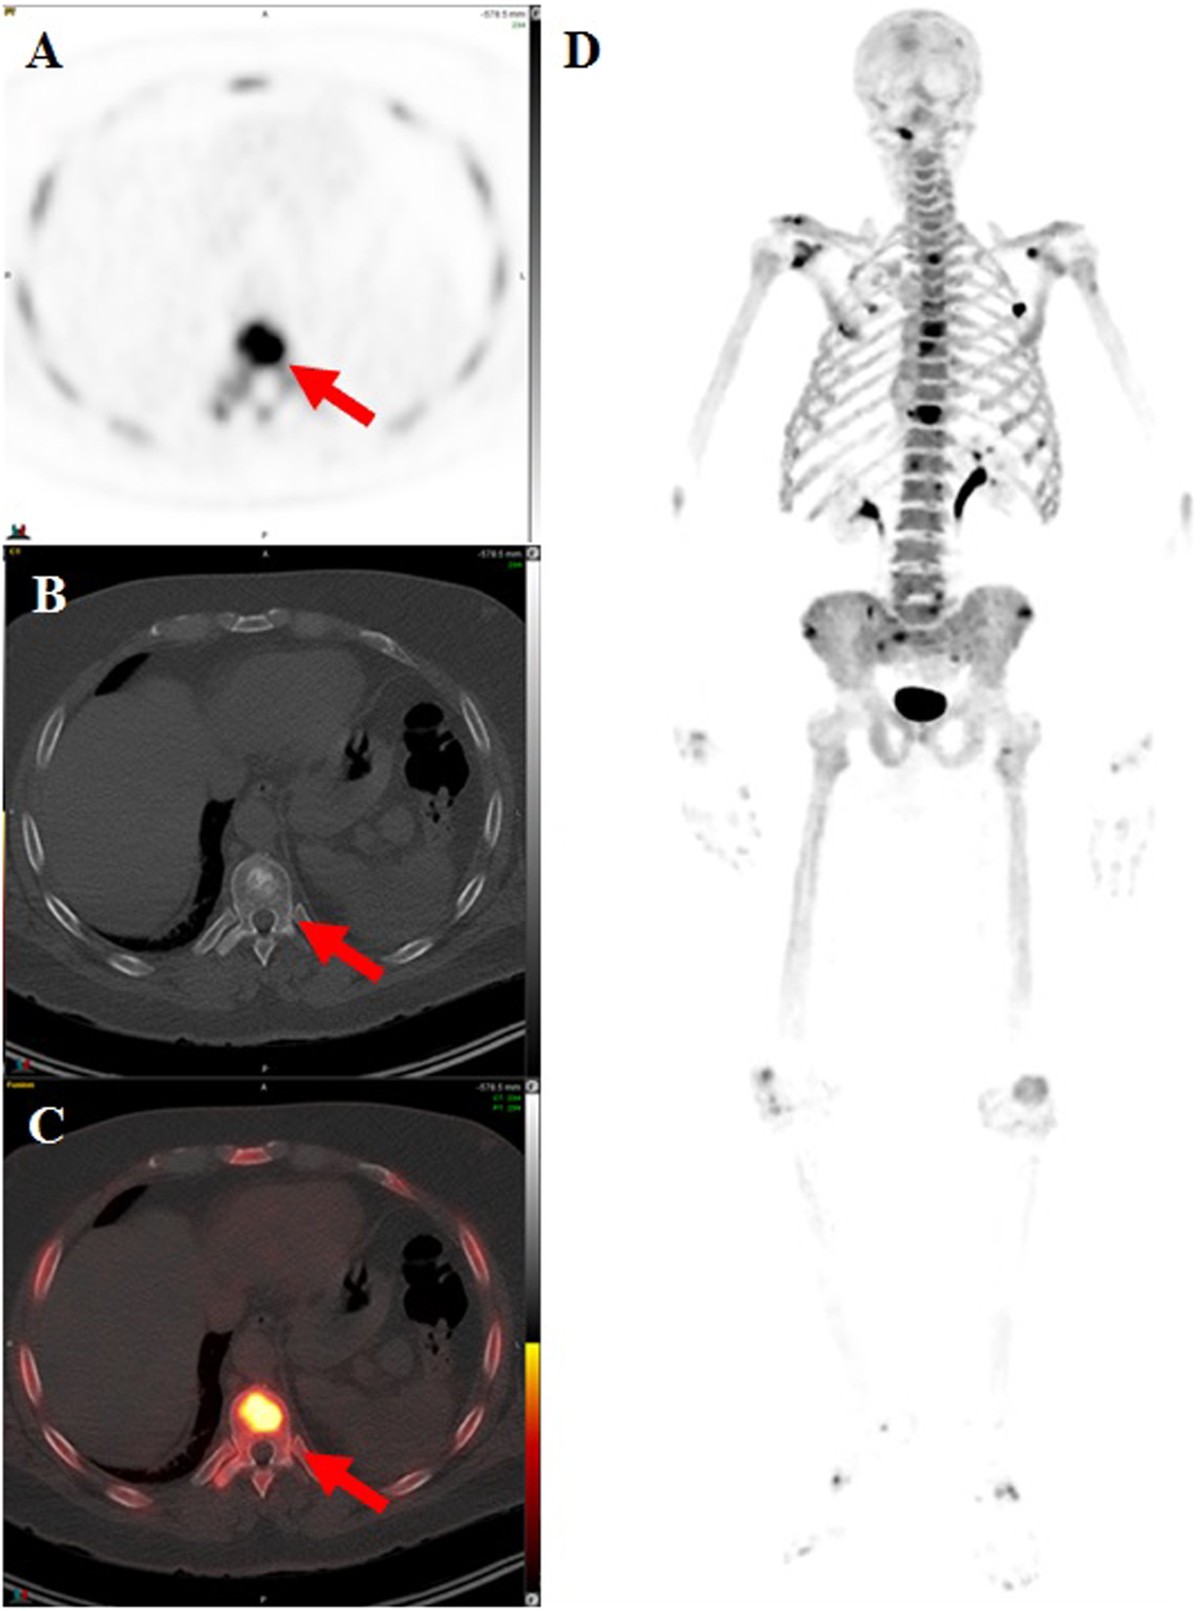

FIGURE 1. | The Detection of Bone Metastases in Patients with High-Risk Prostate Cancer: 99mTc-MDP Planar Bone Scintigraphy, Single- and Multi-Field-of-View SPECT, 18F-Fluoride PET, and 18F-Fluoride PET/CT | Journal of Nuclear Medicine

image size: 1280x672